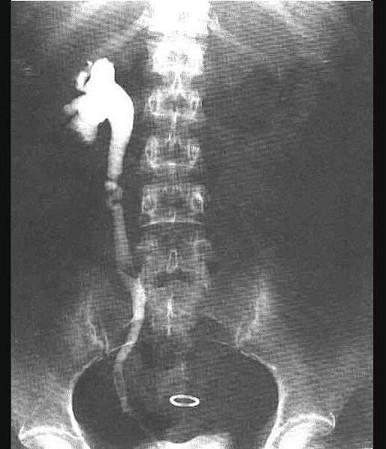

问题 输尿管结石手术前需摄腹部平片,其目的是 ( )

选项 A、作最后结石定位 B、了解双侧肾功能 C、了解尿路有否感染 D、了解结石以下尿路有否狭窄 E、排除泌尿系结核病变

答案 A